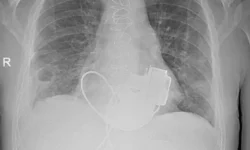

Историческое событие произошло в больнице Сент-Винсента — мужчина 40 лет стал первым в мире, кто покинул медучреждение с полноценно функционирующим титановым сердцем. Проведенная в феврале операция ознаменовала новый этап в борьбе с сердечными заболеваниями. Уникальное устройство с левитирующим ротором поддерживало жизнь пациента 105 дней до успешной трансплантации донорского органа 6 марта.

BiVACOR: технология будущего уже сегодня

Созданное компанией BiVACOR устройство весом 650 г стало плодом 25-летних разработок. В отличие от аналогов, в нем используется единственная подвижная деталь — магнитный пропеллер, работающий без трения. «Этот прорыв перевернул наши представления об искусственных органах», — подчеркнул хирург Пол Янс. Кардиолог Крис Хейвард добавил, что пациент, ранее с трудом преодолевавший 15 метров, теперь вернулся к активной жизни.